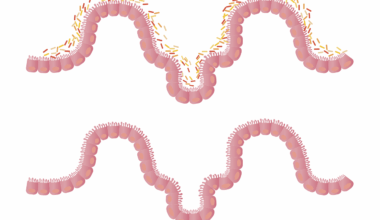

Understanding the functions of progesterone goes beyond its role in reproduction. This hormone assists in regulating menstrual cycles, balancing estrogen, and preventing excessive growth of the uterine lining. In addition to reproduction, progesterone supports neurological functions, influencing mood and well-being. It serves as a natural antidepressant by affecting neurotransmitters, contributing to restful sleep. One of its significant responsibilities is facilitating breast development for lactation. In women, progesterone also helps reduce the risk of endometrial cancer by countering the effects of estrogen. Furthermore, during pregnancy, it helps maintain the uterine environment conducive for fetal development, preventing premature labor. Women’s health extensively revolves around hormonal balance, and progesterone’s stability ensures a smoother transition through puberty, menstruation, pregnancy, and menopause. When levels fluctuate, women may experience various symptoms that disrupt daily life. Addressing these imbalances may include dietary interventions that enhance progesterone production and balance hormones effectively. Proper education about progesterone’s comprehensive role can empower women to take charge of their hormonal health through informed lifestyle choices.